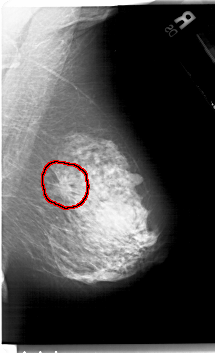

A_1416_1.RIGHT_MLO

FILE: A_1416_1.RIGHT_MLO.OVERLAY

TOTAL_ABNORMALITIES 1

ABNORMALITY 1

LESION_TYPE MASS SHAPE IRREGULAR MARGINS SPICULATED

ASSESSMENT 5

SUBTLETY 4

PATHOLOGY MALIGNANT

TOTAL_OUTLINES 1

BOUNDARY